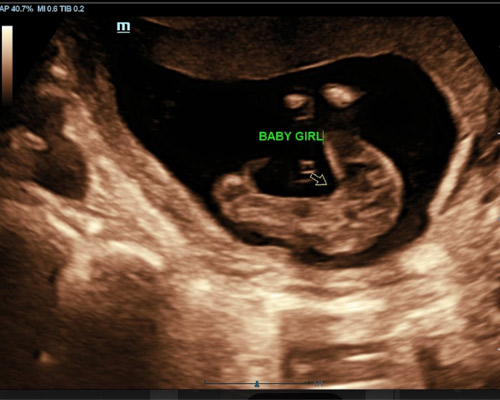

- 2D ultrasound to determine your baby’s gender

During the scan, the sonographer examines the baby’s genital area using ultrasound imaging to identify whether you are expecting a boy or a girl.